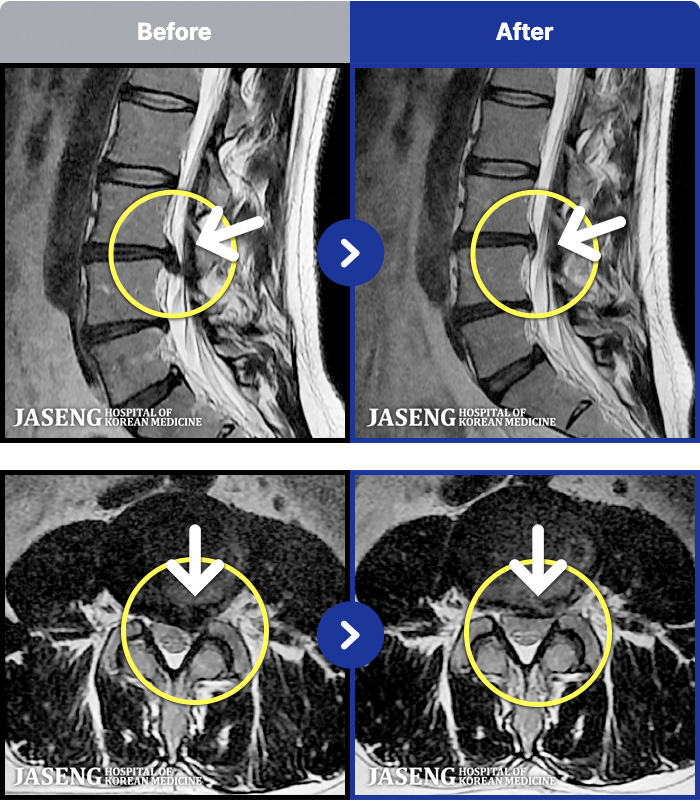

[뱸] 19.11.28~25.05.06